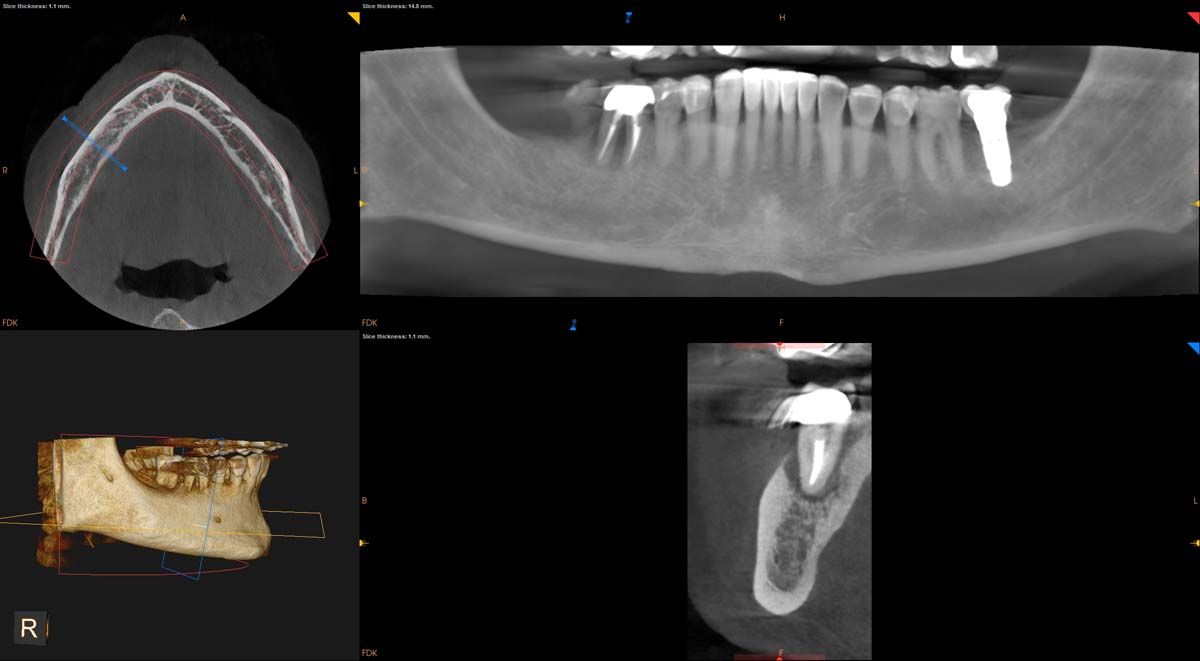

We used to try showing patients their clinical situation on 2D x-rays and demonstrating treatment using models. Later, digital intraoral cameras helped, but they could not show much more than what a patient could see in a mirror. Today, it is possible to show patients every angle of their clinical situation in hyperrealistic 3D with a CBCT scan. Now, when I recommend treatment to patients and they ask why, I am armed with an interactive image captured by my CS 8200 3D extraoral imaging system (Carestream Dental). I scroll through the tooth and bone, point out lesions below the surface, and show why there is or is not enough bone for an implant. If you use something like the Prosthetic-Driven Implant Planning module to automatically merge an intraoral scanner file with the CBCT scan, you create an even more accurate picture. How much easier is it for the patient to accept treatment when they are seeing the end results of that treatment?

The CBCT revealed the extent and solidified the opportunity to make the correct clinical decision